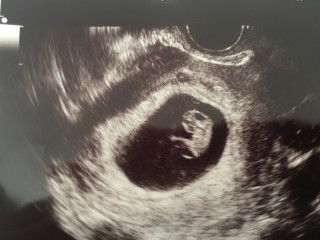

写真:8w3d:チョココロネさん

見方がよく分からないけど、心音聞こえました!

上が8w2d、下が8w3d、別の病院です。

前日は12.6mmで小さいのではないかと不安になっていたのですが、翌日の転院先では14mm以上あると言われてホッとしました。(1日しか違わないのに別の人のエコー写真みたい)

赤ちゃんの角度や測り方によっても変わると言われたので、正確ではないのと誤差も結構あるんだなと勉強になりました。

心臓もしっかり動いていて、「とっても元気」と言ってもらえました。

2cm程の筋腫が2つあるようですが、場所的に問題ないと言われました。